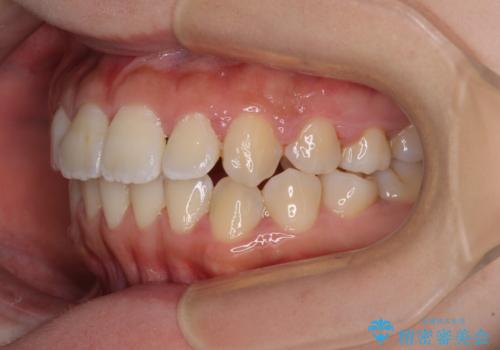

- 上顎歯列と下顎前歯の叢生を気にして来院された患者様です。

上顎からワイヤー矯正を開始し、終了間際から下顎前歯の叢生解消するよう計画しました。

部分矯正でしたが、咬み合わせに違和感が出ることなく気になる部分を改善させることができました。